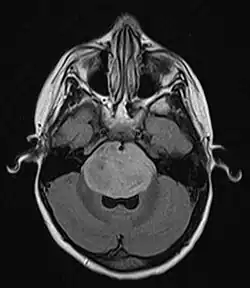

Brain stem glioma. MRI axial, with contrast | |

Neuroimaging, such as MRI, is the main diagnostic tool for brain stem gliomas. In very rare cases, surgery and biopsy are performed.